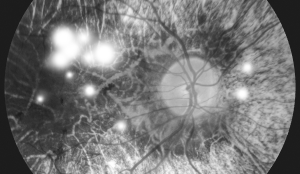

Diabetic Retinopathy

What is Diabetic Retinopathy?

Diabetic retinopathy is a complication of diabetes that occurs in over 40% of patients after 10 years.

It results from damage to the retinal capillaries caused by prolonged high blood sugar levels, leading to impaired peripheral retinal circulation.

This form accounts for about 80% of diabetic retinopathy cases. Blood leaks from the retinal vessels, causing retinal hemorrhages and macular edema. If left untreated, it can progress to proliferative diabetic retinopathy.

Abnormal blood vessels grow on the optic nerve's surface, causing frequent bleeding and scar formation, which can lead to retinal detachment and, in severe cases, blindness.

Diagnosis Methods for Diabetic Retinopathy

• Fundus Photography

• Fluorescein Angiography

• Optical Coherence Tomography (OCT)